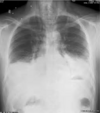

80

What does this CXR show?

* Right mainstem intubation

81